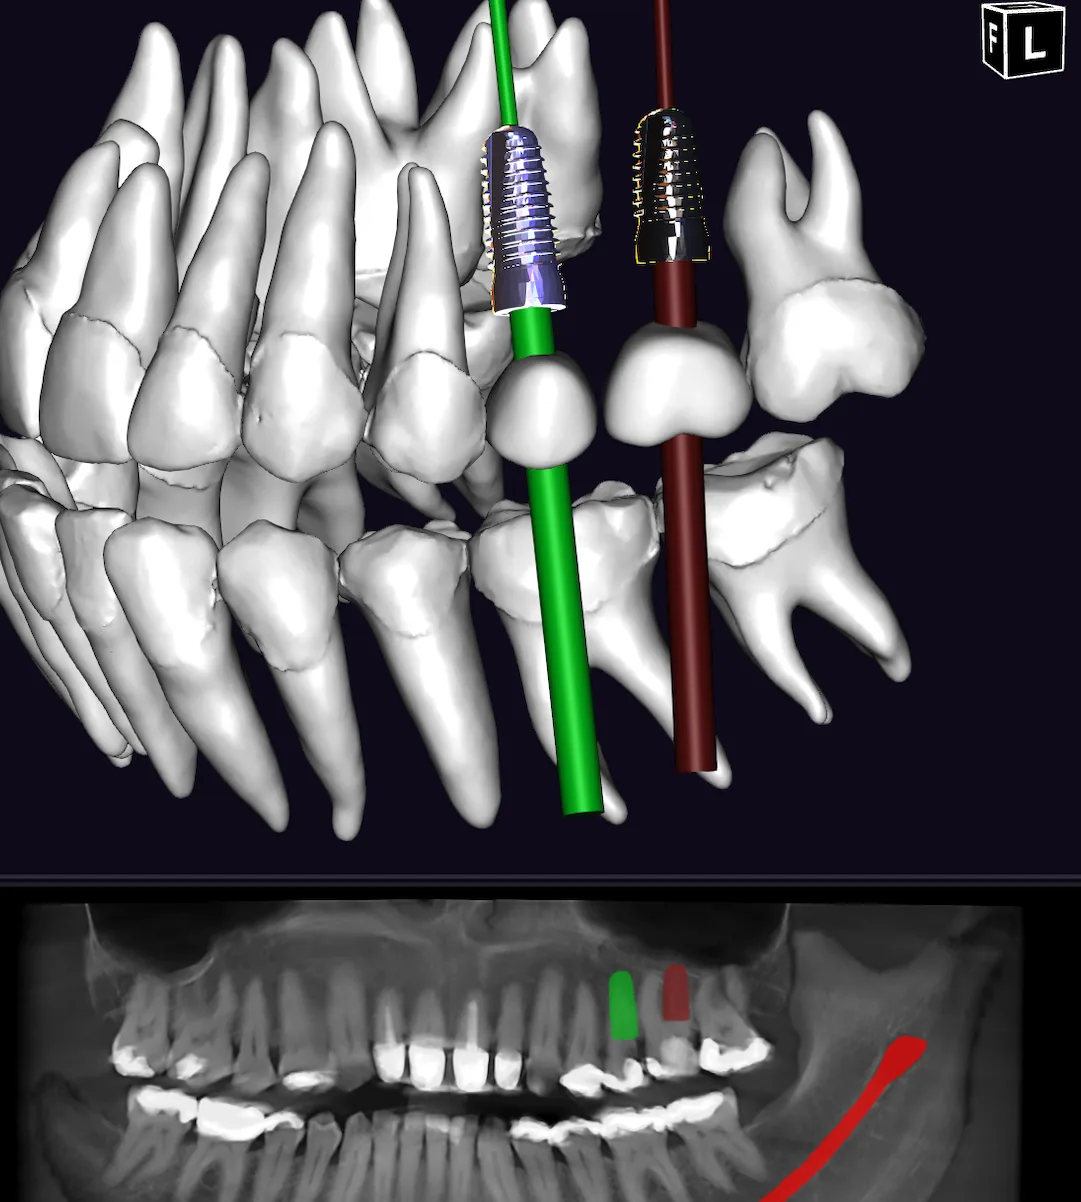

Wir implantieren ausschließlich mit Systemen von Camlog und Straumann — zwei weltweit führende Hersteller mit jahrzehntelanger klinischer Bewährung.

Beide garantieren höchste Qualitätsstandards, biokompatible Materialien und lebenslange Ersatzteilverfügbarkeit.